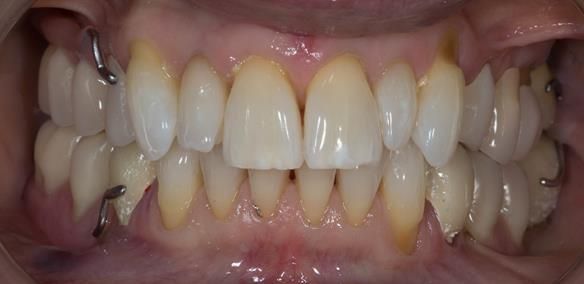

This newsletter describes in step by step detail Angela's transition through immediate partial dentures to crown supported definitive metal based dentures.

This 58 year old woman was referred to me by her general dental practitoner for treatment.

The clinical situation and treatment process is shown in detail below with photographs. I (Finlay Sutton) provided the clinical work and Rowan Garstang provided the technical work.